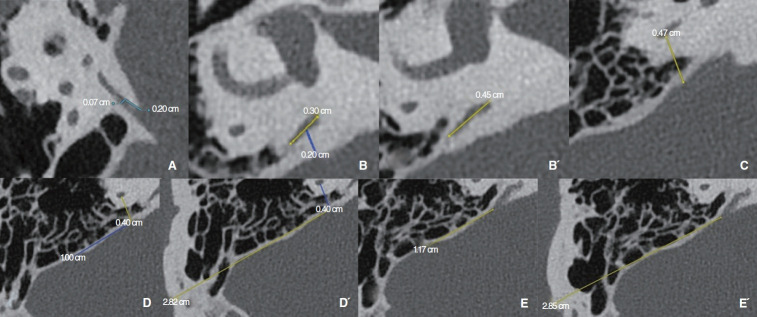

Methods: This retrospective study included 65 patients (126 ears) who underwent temporal bone CT. The Meniere group comprised 26 patients (26 affected ears) meeting the American Academy of Otolaryngology-Head and Neck Surgery (AAO-HNS) criteria for intractable disease; the contralateral ear group included 24 ears, and the control group comprised 39 patients (76 ears) with unrelated conditions. Measurements included VA thickness (A), width (B/B´), the distance between the posterior semicircular canal (PSCC) and posterior fossa (C), PSCC depth (D/D´), and operculum depth (E/E´). Correlations were analyzed, and k-means clustering was applied to classify anatomical variations. Reliability was assessed using intra- and inter-observer tests.